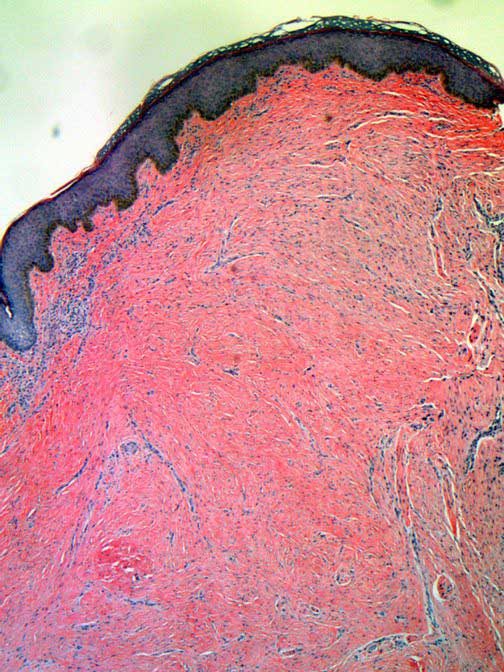

Pathology of Keloid Keloid Removal Expert New York Rubber Band Removal Keloid Timothy mountcastle, offers keloid removal surgery to patients to not only improve their appearance but also to alleviate any pain or discomfort, such as itching, burning, or stinging, related to the keloid. Facial keloids or those that form after a piercing can be cosmetically worrisome. 316k views 8 years ago. Ashburn, va cosmetic surgeon, dr. Learn how to get rid. Rubber Band Removal Keloid.